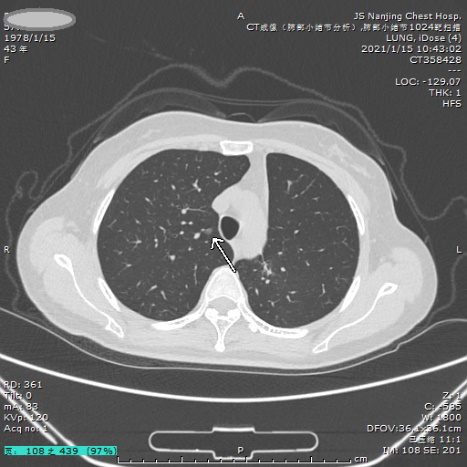

案例四 多发结节